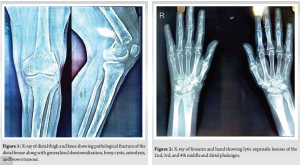

Radiological findings

Radiographs of the thigh revealed a right-sided pathological fracture of the distal femur along with generalized demineralization, bony cysts, osteolysis, and brown tumor (Fig. 1). X-rays of the forearm and hand showed lytic expansile lesions of the 2nd, 3rd, and 4th middle and distal phalanges (Fig. 2). X-ray of the skull revealed multiple lytic lesions with a “salt and pepper” appearance (Fig. 3). Ultrasonography (USG) of the right knee showed an ill-defined hypoechoic heterogeneous lesion on the medial aspect of the lower end of the femur with increased vascularity. USG of the neck revealed an oval iso to a hypoechoic component in the left lower neck, measuring 23.3 × 9.7 × 20.3 mm (Fig. 4). Magnetic resonance imaging of the right knee showed a large mass (7 × 2.9 × 5.8 cm) involving the distal end of the femur, including the diaphysis, metaphysis, and epiphysis, with a pathological fracture, soft tissue edema, and mild fluid collection in the distal thigh (Fig. 5). USG guided fine needle aspiration cytology of the lesion over the right distal femur was done which was suggestive of-giant cell-containing lesion. High-resolution computed tomography of the thorax revealed an expansile osteolytic lesion in the manubrium sterni, right head of the humerus, body of the right scapula, and multiple rib fractures. In addition, hypersensitivity pneumonitis, cardiomegaly, and mild hepato-splenomegaly were noted. USG of the abdomen showed mildly increased periportal echogenicity, a simple cyst (10 × 12 mm) at the midpole of the right kidney, increased bilateral renal echogenicity, and a few mesenteric lymph nodes (average size 10 × 5 mm) with maintained pancreatic hilar architecture. Although a sestamibi scan was highly recommended to confirm the diagnosis of PHPT, it was not performed due to the patient’s low economic status. The provisional diagnosis was a pathological fracture of the right distal femur with secondary osteoporosis at multiple levels caused by PHPT due to a suspected parathyroid adenoma.